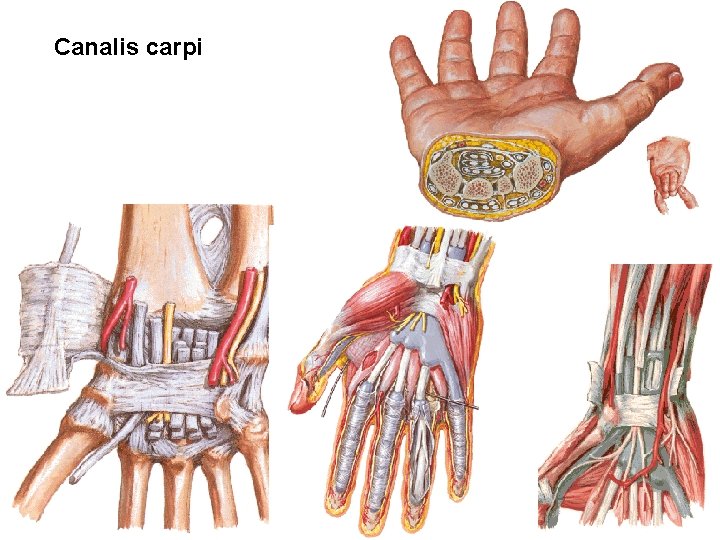

Canalis carpi